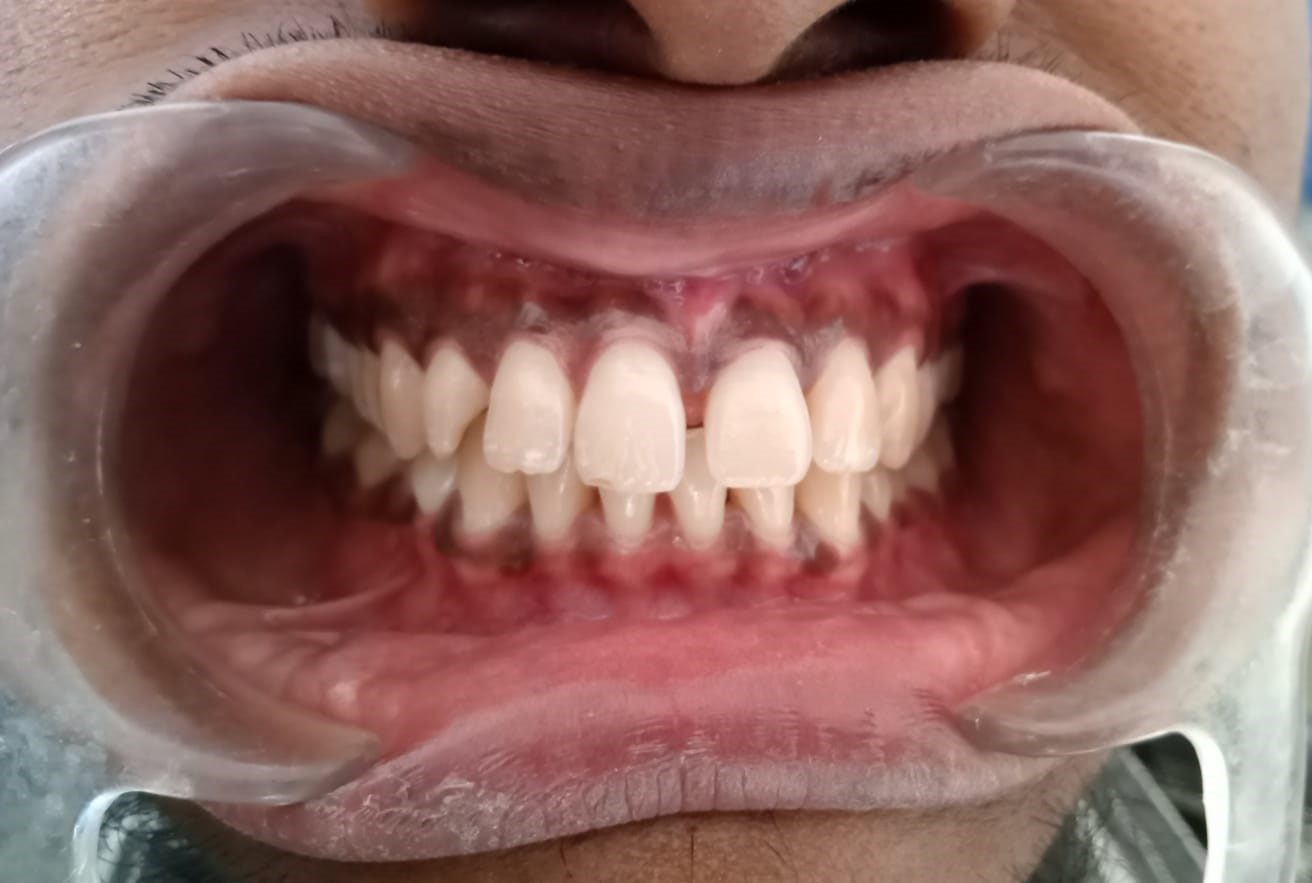

After/Before

See stunning smile transformation before and after

Before After